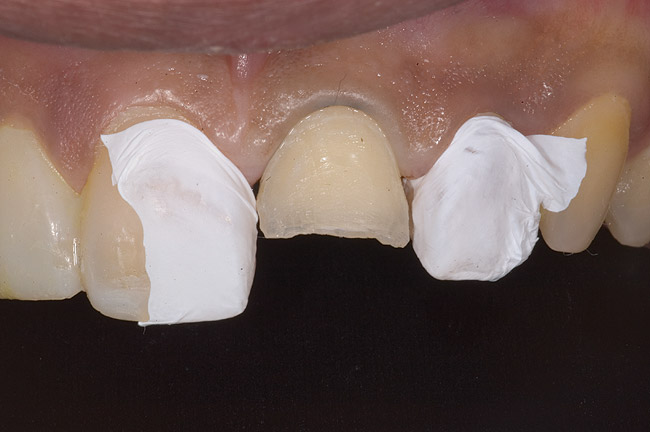

Figure 9: Tooth No. 9 minimally prepared for resin layering on the labial surface.

Figure 9

Figure 10  Tooth No. 9 with no preparation on the palatal surface to restore lost form with bonding resin.

Figure 10

During the next appointment, a palatal index of the approved provisional was fabricated with putty silicone. This enabled the clinician to precisely build the lingual surfaces and incisal edges of teeth Nos. 6 through 11. The provisional mock-up resin on No. 9 was removed, and the underlying labial tooth was roughened with an abrasive diamond bur. No tooth structure was removed from the palatal surface, and unsupported enamel was rounded off from the labial. An ultrathin dry cord was placed in the gingival sulcus on No. 9 (Figure 9 and Figure 10). Teflon tape was used to isolate No. 9 from adjacent teeth. Then 37% phosphoric acid was used to totally etch the labial surface for 10 seconds and the palatal surfaces on No. 9 for 5 seconds. Single bond was applied and spread uniformly across the tooth and light-cured for 20 seconds.